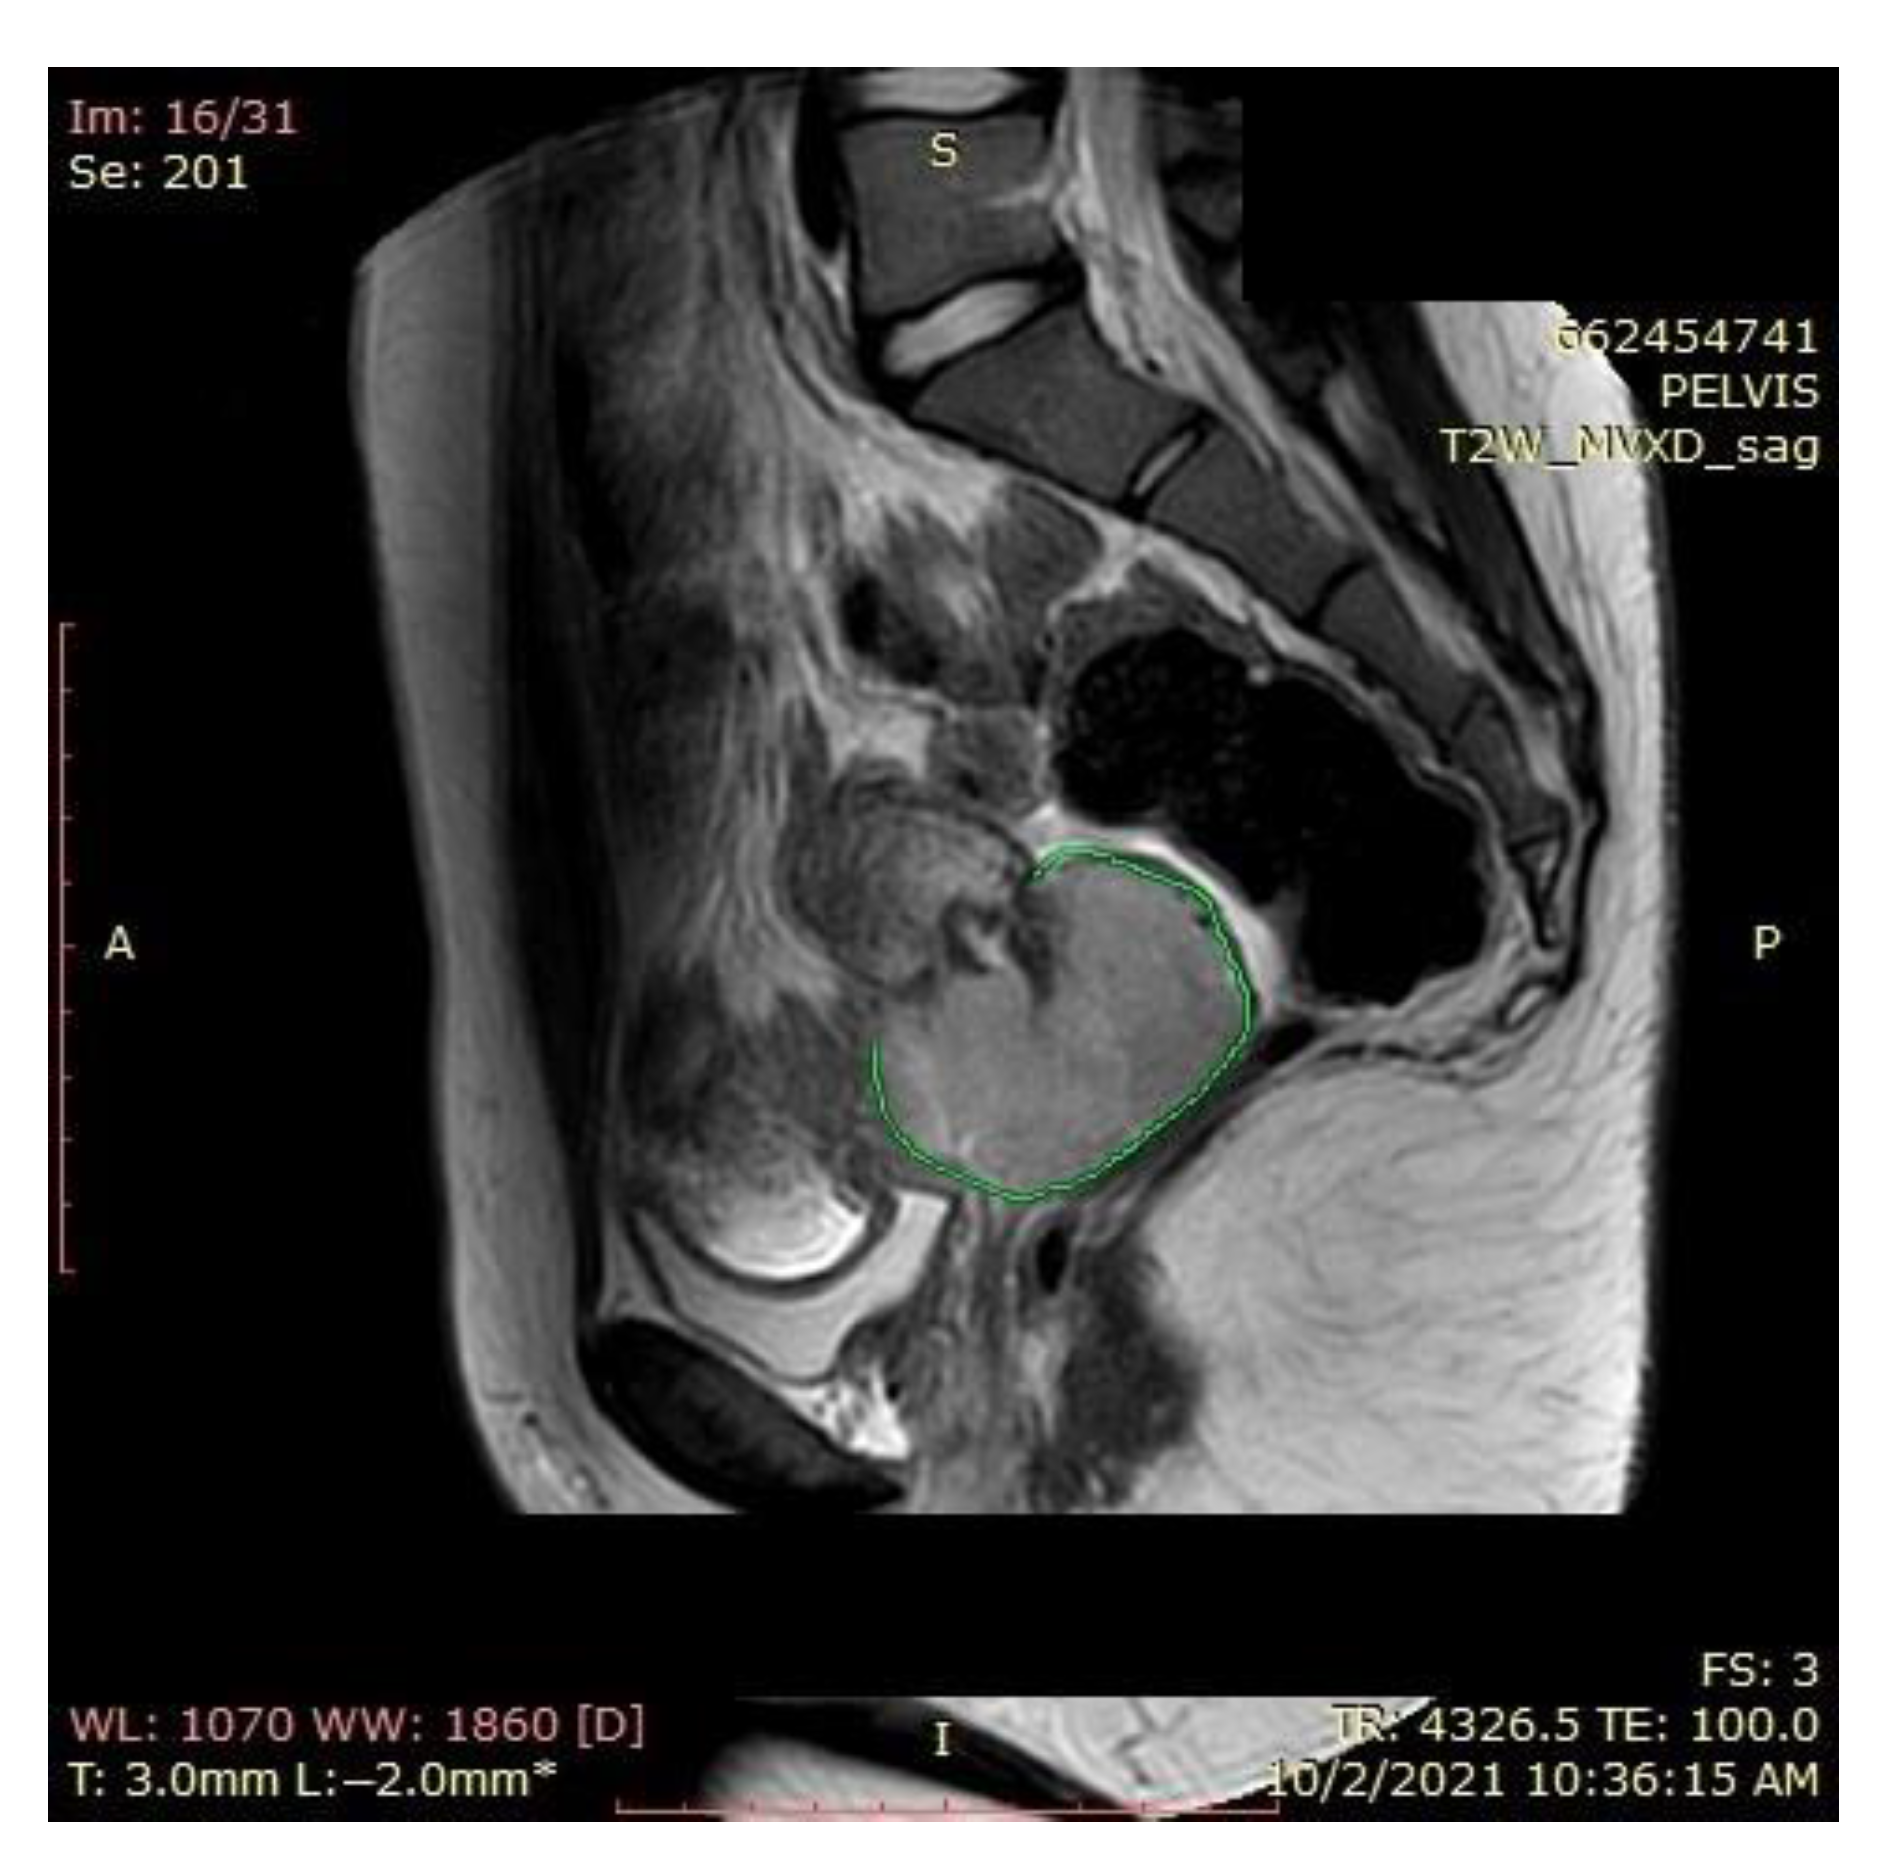

A pelvic MRI was recommended to our patient, as it would be able to provide an accurate anatomic localization of the mass and its relationship with the surrounding organs. It revealed an expansive solid cervical mass that developed between the internal and external cervical orifice, occupying the left vaginal recess, with imprecise boundaries being observed at this level. Axial and sagittal T2-weighted images showed a 53 × 78 × 46 mm mass that was hyperintense compared to normal myometrium, and axial T1-weighted images showed an isointense mass compared to the myometrium that was occupying the uterine cervix and upper vagina. The ovaries and the uterine body were normal in size, and a right external iliac adenopathy was also detected (Figure 1).

An MRI scan performed immediately the next day after finishing the radiotherapy and chemotherapy sessions showed a significant favorable response, with the persistence of a necrotic and ulcerative cervical area and a possible residual lesion on the right side of the cervix (Figure 12).

Due to the persistent residual tumor after radiotherapy and chemotherapy (Figure 13), the patient was referred for intracavitary brachytherapy, achieving favorable evolution and almost complete response (Figure 14). She underwent three sessions of 3D intracavitary and interstitial cervico-uterine brachytherapy, after the insertion of 8 needles Ring and Tandem applicator. All three sessions took place 2 days apart in December 2021, the first one with 7.5 Gy, and the next two with 8 Gy.

Figure 1. Pelvic sagittal T2–weighted sequence: the green highlighted area represents the circumferentially developed cervical tumor mass with intermediate T2 signal that includes both the endo- and the ectocervix protruding into the upper vagina.

Figure 12. Favorable postradiotherapy response with the reduction in cervical mass (the green highlighted area represents the cervical tumoral mass).